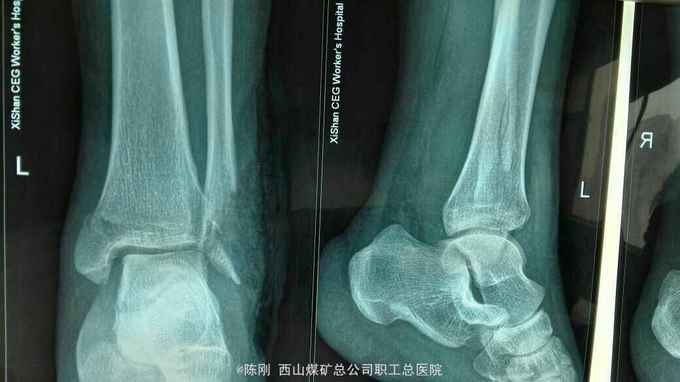

复查x线片

左外踝毁损伤,左肱骨脱位半大结节骨折,左内踝骨折,右内,后踝骨折